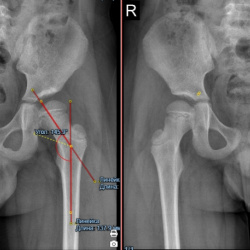

Здравствуйте, подскажите, ребенок 5лет, направили с диагнозом врожденный вывих головки левогобедра слева, 2-сторонний коксартроз. Правильно ли измерил ШДУ, справа Coxa Valga? есть ли признка...

- 1

- 2

- 3

- 4